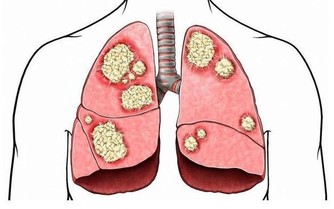

5. 你經常腹脹——可能是小腸細菌過度生長

大家可能都知道,腸道消化要靠好細菌(益生菌),但也有不良細菌在你的消化道內。當好壞細菌之間的平衡被打破時,可能出現小腸細菌過度生長,引發胃腸道內出現多餘的氣體,導致腹脹、腹痛、腹瀉和不明原因的體重增加。